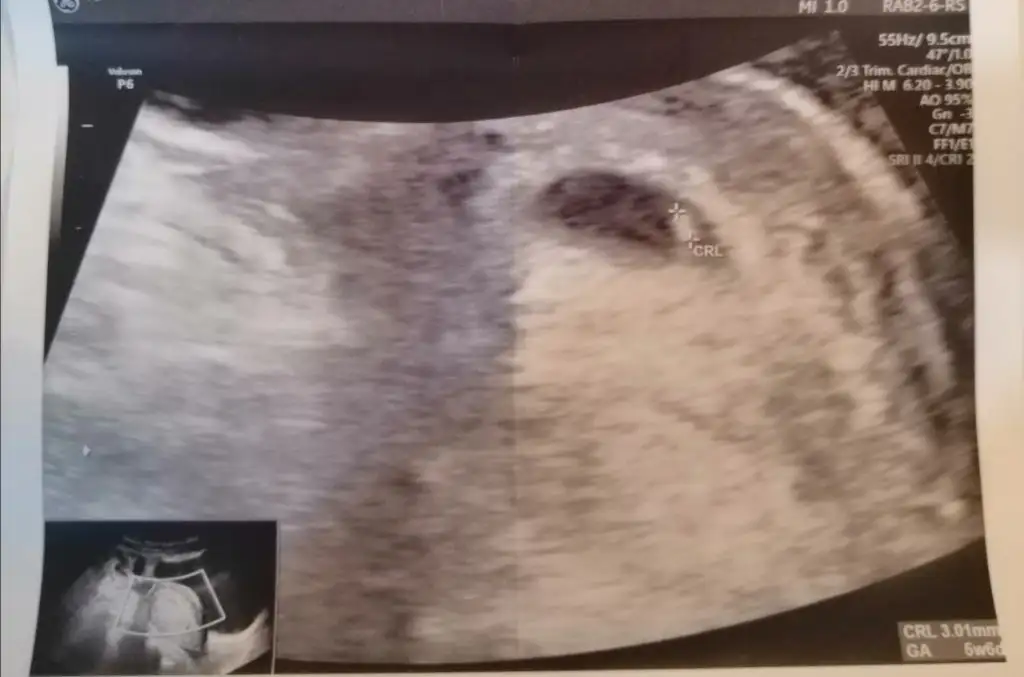

Benim bebiş te 6+6iken karından Ultrason sizin tahmininiz nedir kızlar ☺️

• IMG_20210217_224509.webp

IMG_20210217_224509.webp

26,3 KB · Görüntüleme: 141